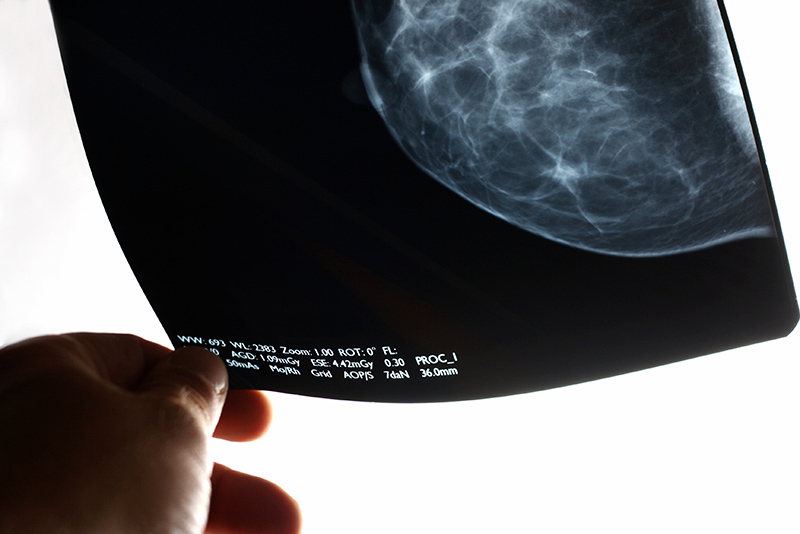

Early Menarche Linked to Breast Cancer in African American Women

Early age at menarche, or the first menstrual cycle, could play a role in the disproportionate incidence of estrogen receptor (ER)-negative breast cancers diagnosed among African American women, according to a study co-authored by a Boston University School of Public Health (SPH) researcher.

The goal was to examine whether relationships between age at menarche and breast cancer are the same for tumors that are ER-positive or ER-negative, particularly among African American women. ER-negative breast cancer is generally more aggressive and known to be associated with a poorer prognosis than ER-positive disease.